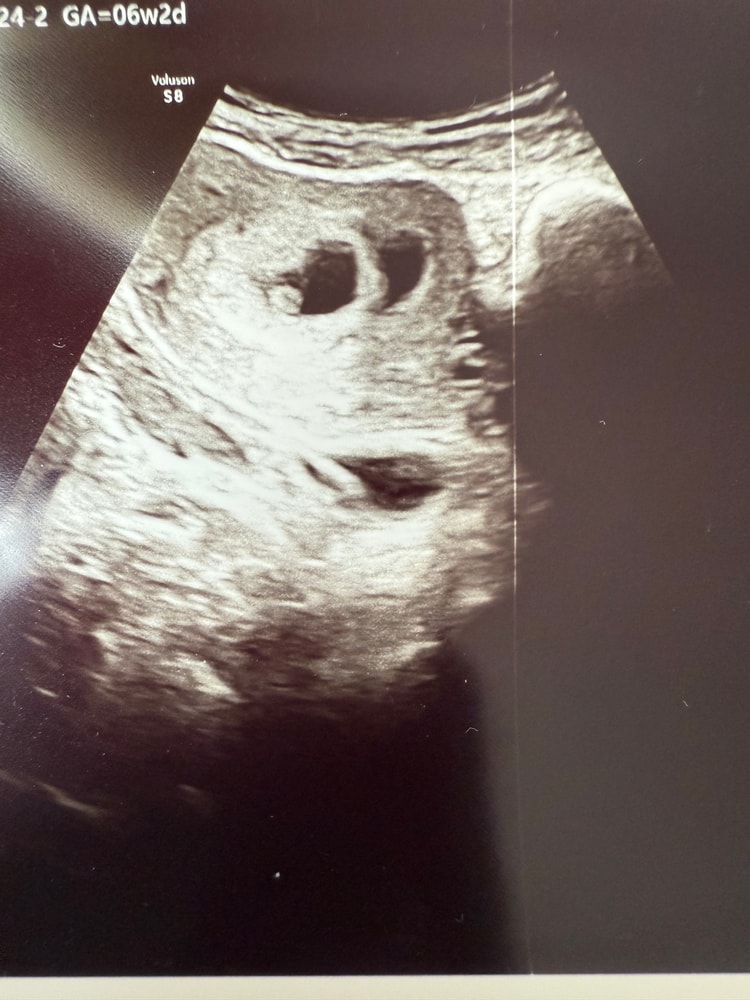

В 6 недель было два ПЯ, в одном был эмбрион с сердцебиением, на трансвагинальном узи обнаружили второе, оно было пустым, врач сказала прийти через неделю, скорее всего второе пя уйдет.